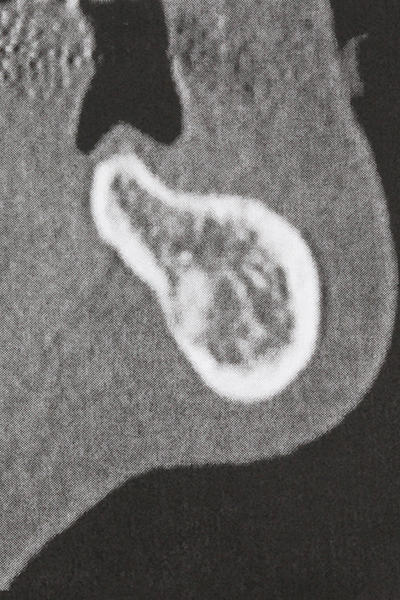

As shown in the past, basically any bone surgery procedure represents a possible indication for piezosurgery. Thus preparation of the mobile segment in distraction osteogenesis (Fig. 23-25) and sandwich osteotomy uses special attachments without endangering the blood supply to the crestal section, which is essential for the success of both techniques (Gonzalez-Garcia, Diniz-Freitas et al. 2008).

For removal of an implant, a vestibular bone cover that is replaced after removal of the implant screw can be prepared to retain the contour of the alveolar ridge.

There are additional applications in sinus surgery. Pathologies and foreign bodies can be removed from the sinus after concentric preparation of a generally trapezoid bone cover in the facial sinus wall. The bone cover is repositioned on conclusion of the intra-antral operation component and secured by wedging or adaptive sutures to prevent dislocation.

Purely orthodontic indications include orthognathic surgery, genioplasty (Fig. 27-30) and orbital decompression in patients with advanced endocrine orbitopathy as a result of Basedow’s disease (Ponto, Zwiener et al. 2014). Piezo devices are also used in maxillofacial surgery and to remove tumours at the base of the skull in various hospitals.